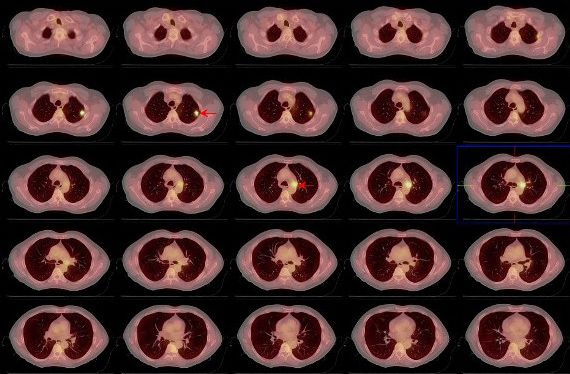

Se indica estudio PET de cuerpo entero y PET-CT torácico para investigar los hallazgos previos. Tanto en el primero (fig. 1) como en el PET-CT torácico (figs. 2, 3 y 4), se detecta acúmulo patológico de la FDG en lóbulo pulmonar superior izquierdo (2 cm, SUVmax=4,2) que se interpreta como un implante nodular maligno. En mediastino se comprueba captación patológica de la FDG en región perihiliar izquierda (2,5 cm, SUVmax=4,1) que corresponde probablemente a una adenopatía mediastínica maligna.

Ante los hallazgos del PET corporal y PET-CT torácico se decide realizar nuevamente con éxito una PAAF pulmonar. La AP informó un carcinoma indiferenciado de pulmón de células pequeñas. Tras el diagnóstico de segundo tumor pulmonar, se decide administrar tratamiento concomitante de RT locoregional y quimioterapia (QT) con Cisplatino y VP6, a un total de 6 ciclos. Recibe tratamiento de RT locoregional sobre el nódulo pulmonar superior izquierdo y ganglios regionales a razón de 2Gy/día, 5 días a la semana hasta un total de 60Gy. Posteriormente y estando el paciente asintomático, se solicita PET corporal y PET-CT torácico de reestadiaje y de valoración de respuesta terapéutica.

Tanto en el estudio PET corporal (fig. 5) como el PET-CT torácico (fig.6) se detecta la ausencia de hallazgos significativos en lóbulo pulmonar superior izquierdo y en regiones ganglionares hilio-mediastínicas, lo cual refleja una muy buena respuesta al tratamiento concomitante de QT y RT y por tanto remisión completa de la enfermedad.